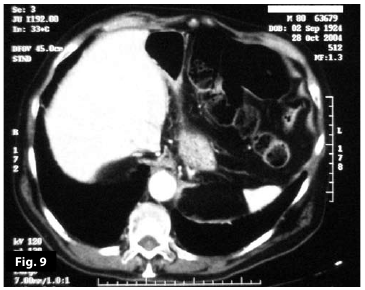

Figure9

Figure10

Figure9-10